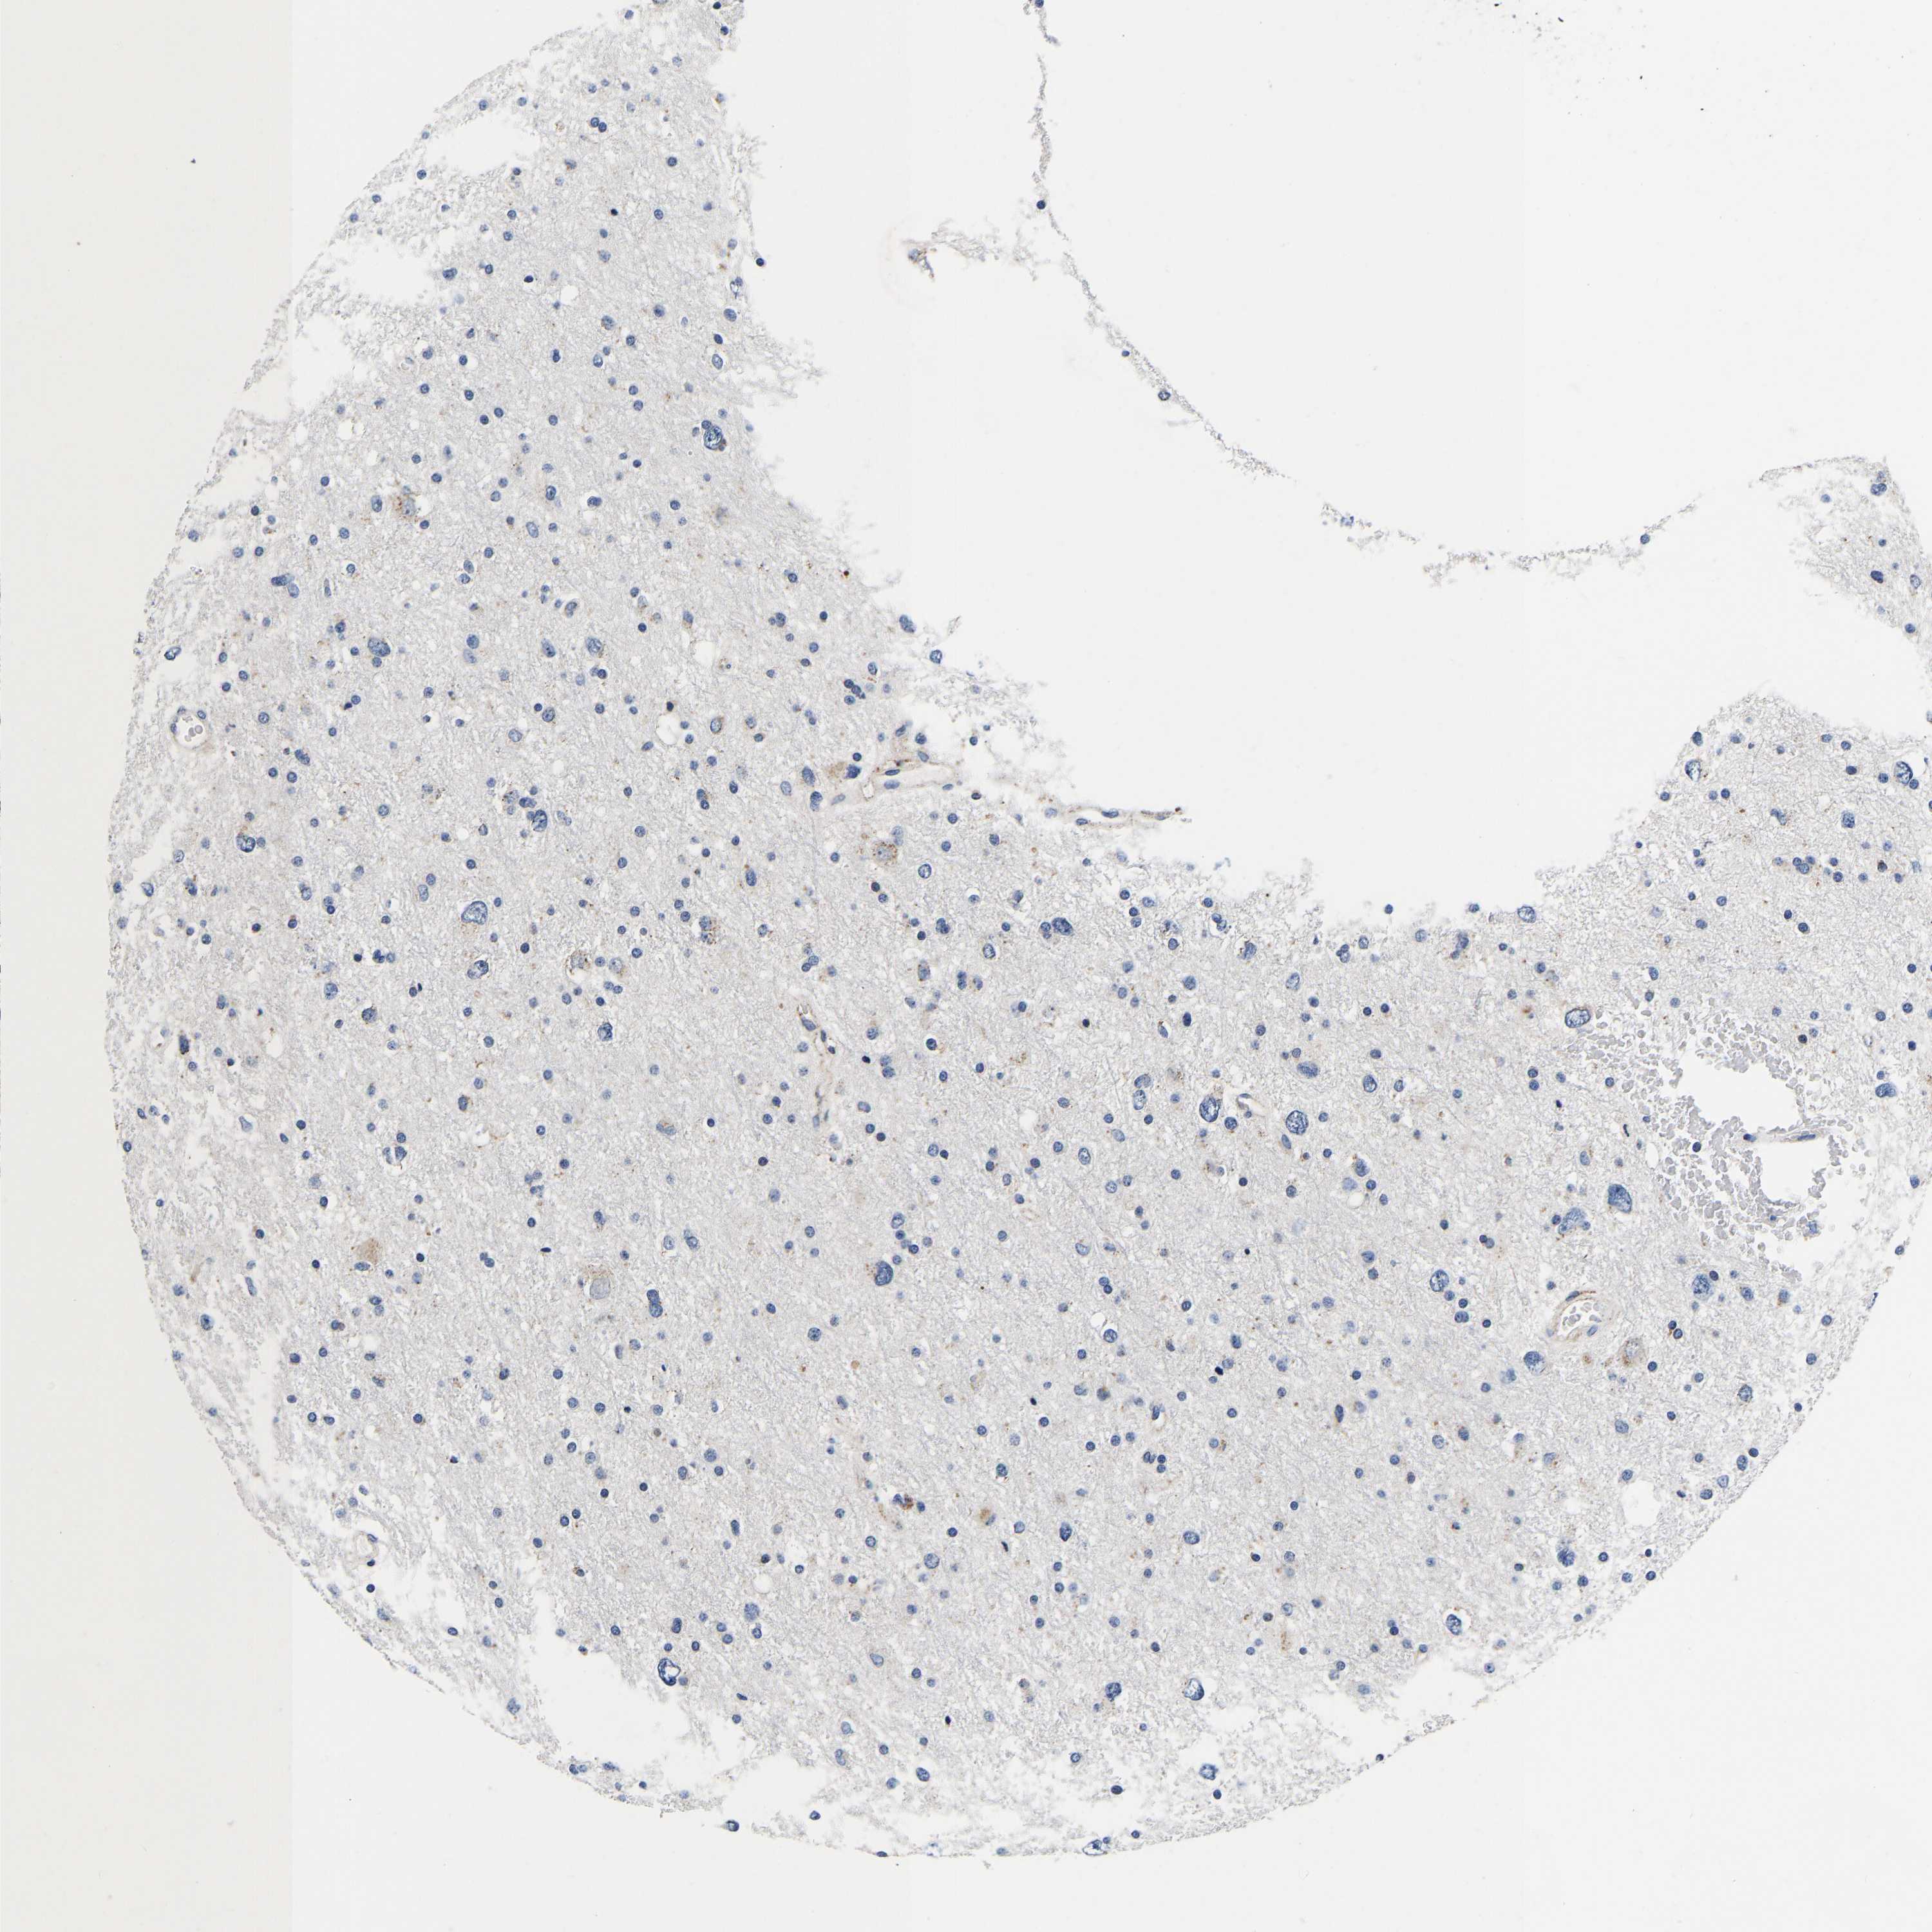

GLIOMA - Protein expressioni

A mouse-over function shows sample information and annotation data. Click on an image to view it in a full screen mode. Samples can be filtered based on level of antibody staining by selecting one or several of the following categories: high, medium, low and not detected. The assay and annotation is described here.

Note that samples used for immunohistochemistry by the Human Protein Atlas do not correspond to samples in the TCGA dataset.

Antibody stainingi

Antibody staining in the annotated cell types in the current human tissue is reported as not detected, low, medium, or high, based on conventional immunohistochemistry profiling in selected tissues. This score is based on the combination of the staining intensity and fraction of stained cells.

Each image is clickable and will lead to virtual microscopy that enables deeper exploration of all samples and also displays staining intensity scores, fraction scores and subcellular localization as well as patient and tissue information for each sample.

Antibody HPA008763

Antibody HPA028747

Antibody CAB019394

Staining

High

Medium

Low

Not detected

Intensity

Strong

Moderate

Weak

Negative

Quantity

>75%

75%-25%

<25%

None

Location

Nuclear

Cytoplasmic/membranous

Cytoplasmic/membranous,nuclear

Glioma, malignant, High grade

Glioma, malignant, Low grade